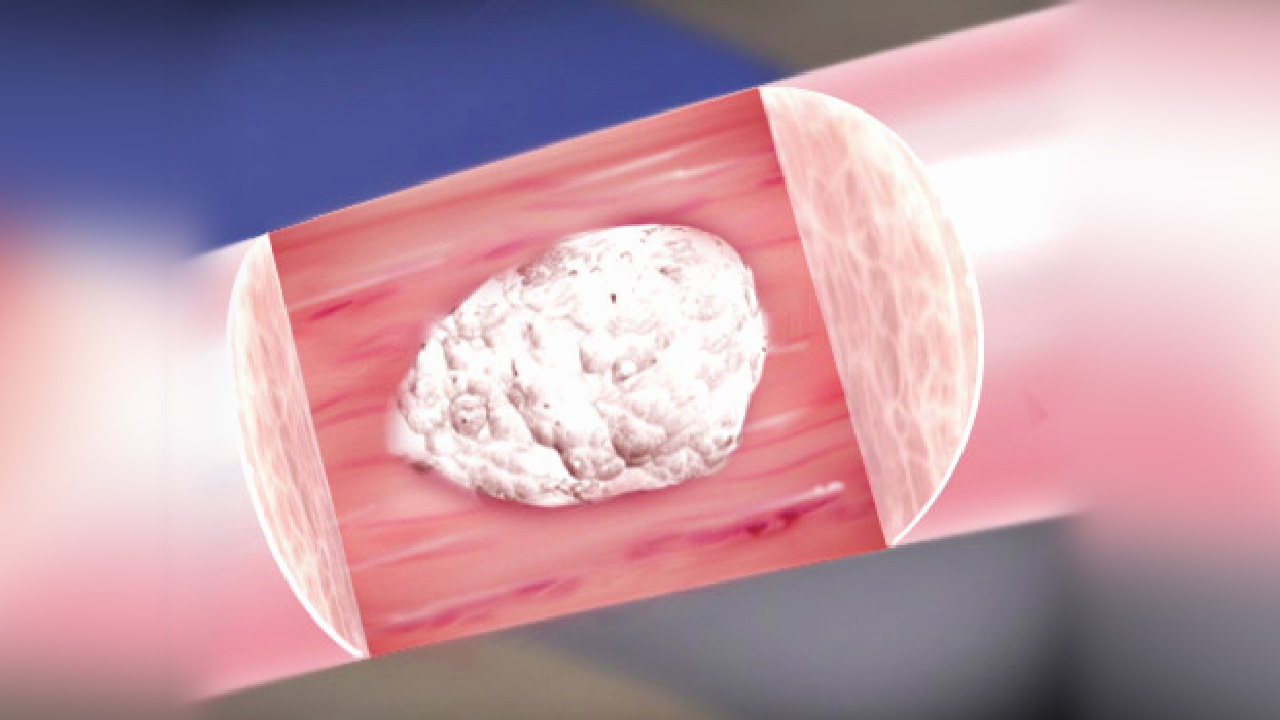

You can do this by: To protect your oasis it’s essential to remove all calcium deposits. Below are a few options that break down calcium deposits.